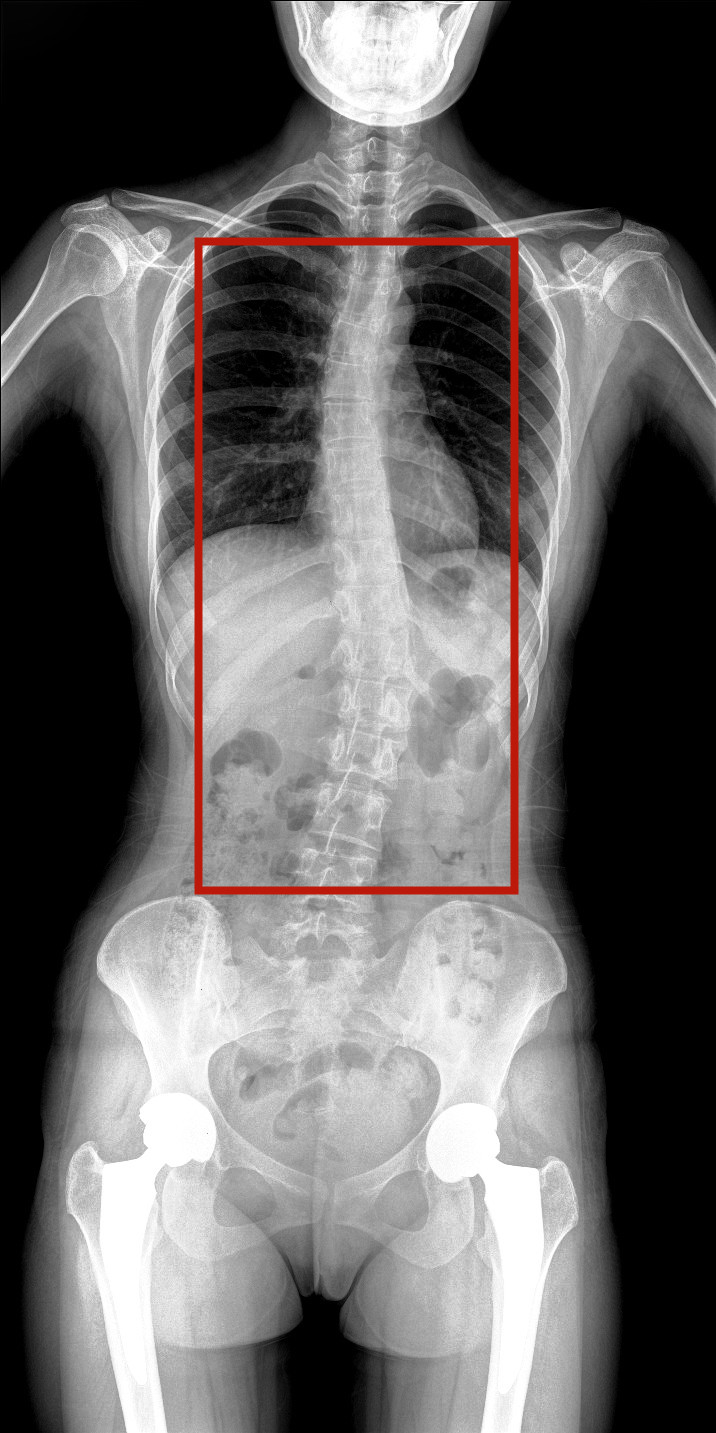

病情描述:患者,女,23歲,免疫系統(tǒng)畸變導(dǎo)致的脊柱側(cè)彎

虛線框示患者脊柱側(cè)彎明顯

脊柱圖像范圍包含脊椎、雙側(cè)肩部及骨盆。片內(nèi)頸椎、胸椎、腰椎、骶椎、雙肩及骨盆重組影像結(jié)構(gòu)清晰,對(duì)比度高,對(duì)位、對(duì)線好,接緣區(qū)無(wú)重疊、遺漏、縫隙。能夠滿足臨床測(cè)量脊柱Cobb角及臨床人體平衡線等指標(biāo)的測(cè)量,整體上能對(duì)全脊柱進(jìn)行觀察診斷。